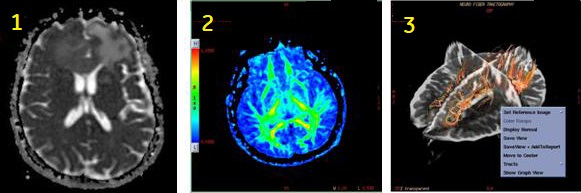

| Number | Description |

|---|---|

| 1 | DTI ADC map |

| 2 | DTI Fractional Anisotropic map |

| 3 | Fibertrak image generated in READY View |